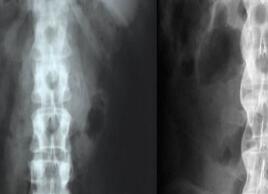

强直性脊柱炎是有一些认识的,该病带来的困扰较多,并且给他们的健康带来了特别多的伤害,生活当中有很多的原因可以诱发强直性脊柱炎的出现,这是我们要多去了解的知识了,来了解一下强直的病因有哪些呢。贵阳看强直的医院

贵阳治疗强直上述中的这些内容带大家了解到了可以引发强直性脊柱炎的原因是什么了,这种疾病会让患者的生活无法自理,而且给他们的健康带来了极强的伤害,所以说我们要认真去了解该病的发病原因,注意展开一些强直性脊柱炎的预防工作。